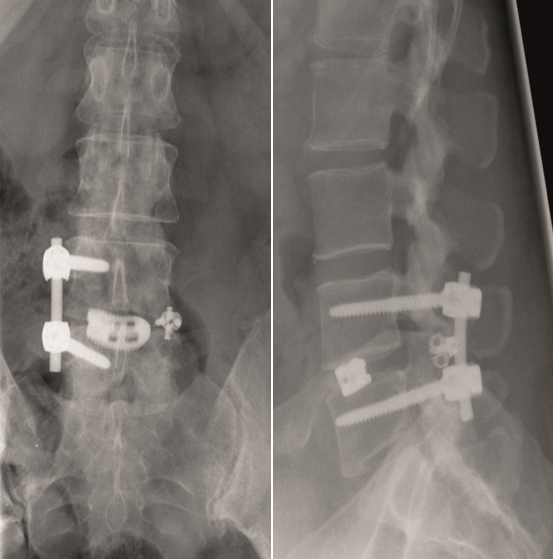

A 45-year-old healthy male patient experienced load dependent lower back pain (LBP) for 6 years, with no radicular pain and no neurologic deficit.

Multilevel facet pathology is shown in Fig 6. Intraoperative and postoperative images are shown (Fig 7-9).